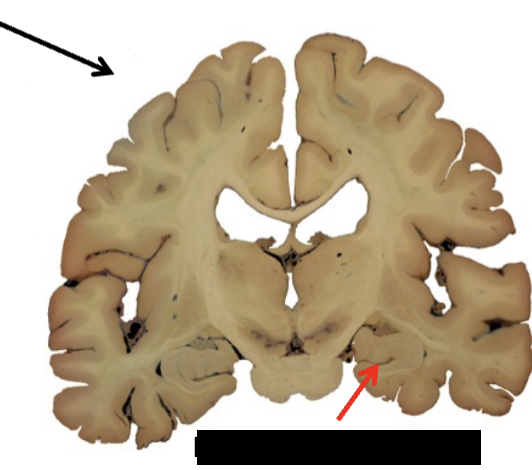

limbic system

what structure is this?

amygdala

hippocampal formation

what are the three parts of the hippocampal formation?

dentate gyrus, hippocampus, and subiculum